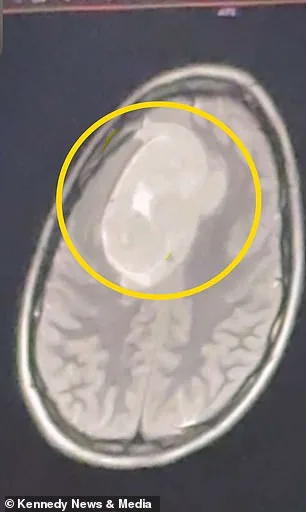

During a Christmas break visit, a second doctor ordered an MRI scan in January 2026. The results revealed a benign brain tumor the size of a tennis ball, pressing on her left frontal cortex. This area governs executive function, motor control, and language. Doctors issued an urgent warning: 'Go to the emergency room immediately,' they said, as untreated pressure risked irreversible cognitive and motor impairments.

Keating's tumor, which had been growing for three to four years, was removed via a six-hour craniotomy. Surgeons extracted the mass but left a scar across her scalp. The National Brain Tumor Society reports 67,000 new benign brain tumor diagnoses annually in the U.S., with 1 million people living with such conditions. Keating now faces radiation therapy and a postponed college graduation, her original spring timeline derailed by the surgery.